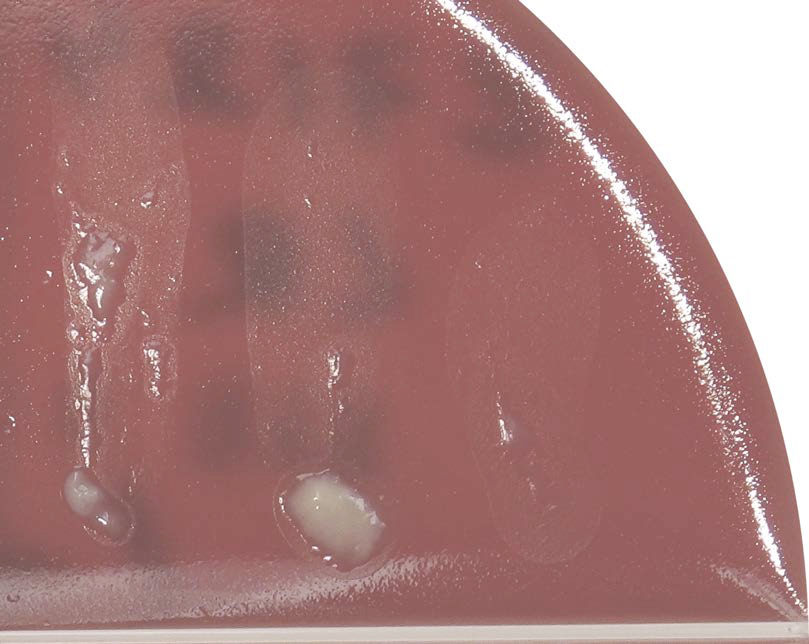

Esculin reaction

Culture media that contains esculin the (Focus®/MTKT portion of the Tri-plate in our lab) is used to differentiate Enterococci and group D Streptococci based on their ability to hydrolyze esculin. When an organism hydrolyzes the glycoside esculin to form esculetin and dextrose, the esculetin reacts with the ferric citrate in the media to produce a dark brown or black phenolic iron complex. A UV light may be used to more clearly visualize the reaction, although it can be seen without the UV light.

Esculin + |

Esculin – |

Esculin Variable |

|---|---|---|

| Enterococcus sp. | Strep agalactiae | Aerococcus sp. |

| Strep. uberis | Strep dysgalactiae | |

| Lactococcus sp. |

This is a useful test because the majority of esculin-positive Strep and Strep-like organisms (not Aerococcus) are typically more pathogenic than the non-ag/non-hemolytic esculin-negative Streptococcus dysgalactiae. Streptococcus uberis, Enterococcus and Lactococcus are more difficult to cure and more likely to cause chronic mastitis.